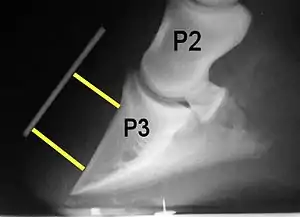

Rotation is the most common form of displacement, and, in this case, the tip of the coffin bone rotates downward.[4] The degree of rotation may be influenced by the severity of the initial attack and the time of initiation and aggressiveness of treatment. A combination of forces (e.g. the tension of the deep digital flexor tendon and the weight of the horse) result in the deep digital flexor tendon literally pulling the dorsal face of the coffin bone away from the inside of the hoof wall, which allows the coffin bone to rotate. Also, ligaments attaching the collateral cartilages to the digit, primarily in the palmar portion of the foot, possibly contribute to a difference in support from front to back. The body weight of the animal probably contributes to rotation of the coffin bone. Rotation results in an obvious misalignment between PII (the short pastern bone) and PIII (the coffin bone). If rotation of the third phalanx continues, its tip can eventually penetrate the sole of the foot.

Radiographs

Radiographs are an important part of evaluating the laminitic horse. They not only allow the practitioner to determine the severity of the episode, which does not always correlate with degree of pain,[1] but also to gauge improvement and response to treatment. Several measurements are made to predict severity. Additionally, radiographs also allow the visualization and evaluation of the hoof capsule, and can help detect the presence of a lamellar wedge or seromas.[1] The lateral view provides the majority of the information regarding degree of rotation, sole depth, dorsal hoof wall thickness, and vertical deviation.[1][17] A 65-degree dorsopalmar view is useful in the case of chronic laminitis to evaluate the rim of the coffin bone for pathology.[1]

Several radiographic measurements, made on the lateral view, allow for objective evaluation of the episode.

- Palmar angle (PA): the angle between a line perpendicular to the ground, and a line at the angle of the palmar surface of P3.

- Horn:lamellar distance (HL): the measurement from the most superficial aspect of the dorsal hoof wall to the face of P3. 2 distances are compared: a proximal measurement made just distal to the extensor process of P3, and a distal measurement made toward the tip of P3. These two values should be similar. In cases of rotation, the distal measurement will be higher than the proximal. In cases of distal displacement, both values will increase, but may remain equal. Therefore, it is ideal to have baseline radiographs for horses, especially for those at high-risk for laminitis, to compare to should laminitis ever be suspected. Normal HL values vary by breed and age:[1]